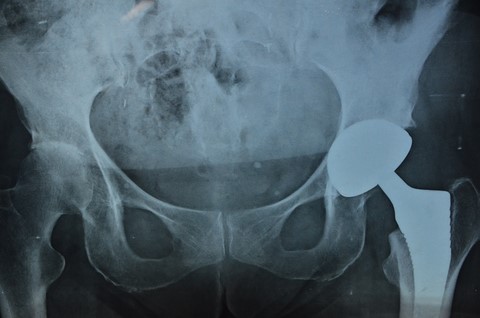

Le 22, retour en camper d'accasion à Nafplio pour Françoise, skippé par Renée et Hubert pour avoir des radios de sa hanche!

Bingo, l'arthrose s'est developpée à l'autre hanche. Photo, d'un érotisme torride, de l'intimité de la femme de ma vie:

Encore une saison entachée par des problèmes de santé.

Avouons le, c'est un poil pénible. Mais il faut faire avec.